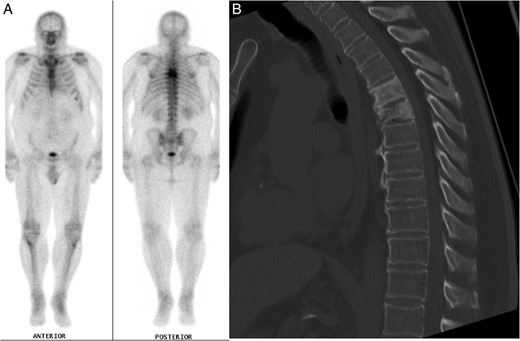

The patient's past medical history included essential hypertension and type 2 diabetes mellitus treated with metformin. Mid-thoracic back pain had also been an active medical problem, which had been under investigation for over 1 year, following a fall. A full blood count had identified lymphopenia and a normocytic, normochromic anaemia. Electrolytes and creatinine, liver function tests, thyroid function tests, vitamin B12, folate, adrenocorticotrophic hormone (ACTH) and cortisol levels were all normal. A computed tomography (CT) scan of his thoracic spine revealed T5 and T6 vertebral crush fractures, with 30–40% loss of height of T6, for which he had been on calcium, vitamin D supplements and zoledronic acid injections. He had not been taking corticosteroid medications and denied previous steroid use. The T5 and T6 thoracic fractures had the appearance of underlying mixed lytic and sclerotic lesions suggestive of neoplasia. A nuclear medicine bone scan highlighted the thoracic lesions but did not identify other sources of abnormal tracer uptake (Fig. 1A and B). A CT scan of the chest, abdomen and pelvis did not detect any other pathology. A T6 vertebral bone biopsy had also been taken a few months prior to this presentation, which only showed reactive bone and cartilaginous fragments with no tumour cells isolated. Tumour markers were negative apart from a β2-microglobulin level of 3.1 mg/l (reference range 0.7–1.8 mg/l).

(A) Nuclear medicine bone scan demonstrating tracer uptake in the T5 and T6 vertebral fractures with no evidence of other abnormal uptake. (B) Mid-sagittal CT scan of the thoracic spine during clinical presentation with ataxia, displaying the vertebral crush fractures and SEL.